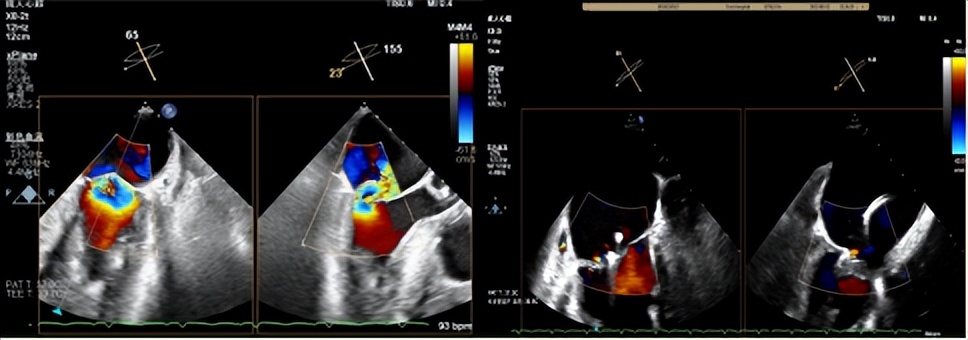

患者男性,71岁,反复心衰发作,心脏彩超示重度二尖瓣返流(MR 4+)(图二、三),既往糖尿病病史10余年、单侧颈内动脉闭塞7年余,2年前行冠脉搭桥及主动脉动脉瘤支架植入术,本次心衰急性发作合并严重肺部感染,经口气管插管呼吸机辅助并对症药物治疗,效果欠佳;存在较高心功能进一步恶化、呼吸循环衰竭、恶性心律失常、猝死等风险。

图二(食道超声心动图二尖瓣大量返流)

食道超声显示术后即刻效果显著,心房侧未见返流信号(图九),3D显示二尖瓣呈组织桥形态良好的双孔状,返流消失(图十),临床症状明显改善,术后效果堪称完美。

图九(左:术前大量反流 右:术后心房侧未见明显返流信号)